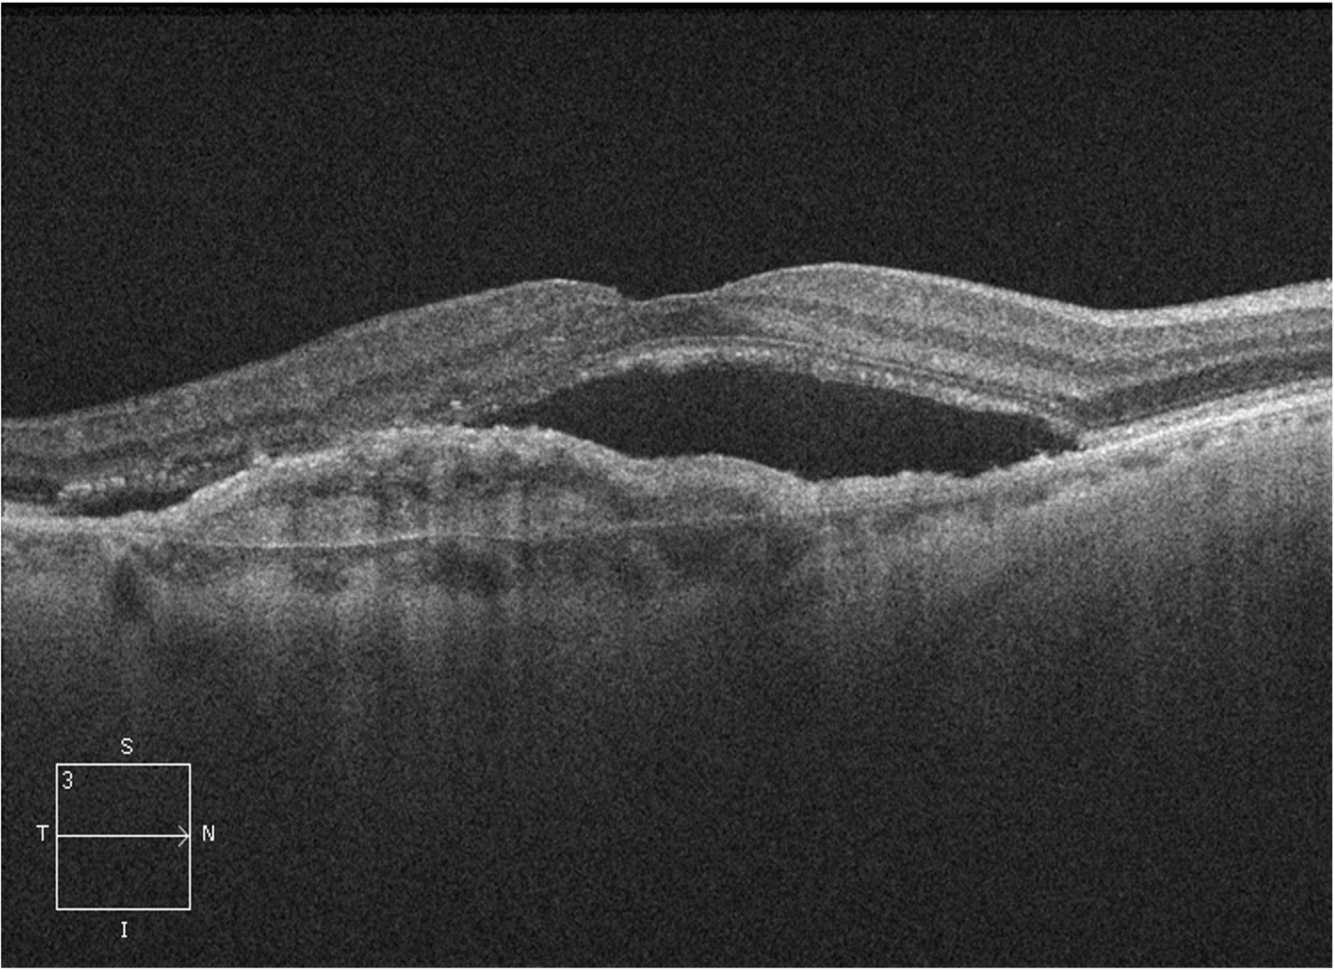

14

Q

A

In this image, the dark area is beneath the retina, but inner to the RPE – this demonstrates subretinal fluid.

There is also an elevated region beneath the retinal pigment epithelium, which indicates the presence of a neovascular membrane.